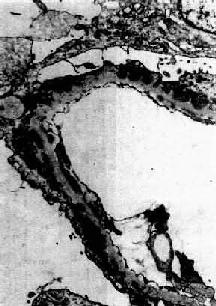

图12-18 膜性肾小球肾炎

电镜下见肾小球毛细血管基底膜表面,上皮细胞下电子致密沉积物,基底膜向表面突出伸入沉积物之间,上皮细胞足突融合